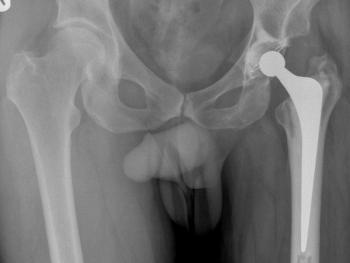

Clinical cases: variations of Exeter stem size and offset copes with almost all abnormal anatomies.

Figure 11 & Figure 12: Cemented fixation in poor bone has the immediate advantage of full weight-bearing in frail patients, especially after trauma.